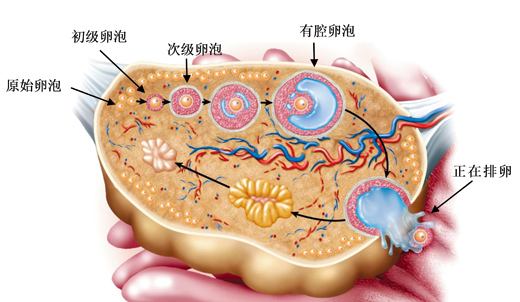

正常育龄期妇女的卵巢在下丘脑—垂体—卵巢轴(HPO轴)的作用控制下,每月都会发生规律月经和排卵。当一些疾病干扰HPO轴导致卵巢功能异常时,就会出现不排卵。不排卵的...

卵泡发育不好一直是困扰多数备孕夫妻的大难题,一般在月经正常卵泡发育为1.8-2.0CM左右为优势卵泡,卵泡发育不良会影响受孕几率,甚至会不孕。卵子发育不良的女性要...

很多不孕症的患者,在诊治的过程中都经历过一次或数次的药物促排卵。特别是试管婴儿的患者,在一个月经周期内,通过控制性超促排卵和取卵手术,获得了5-20个左右的卵子。...